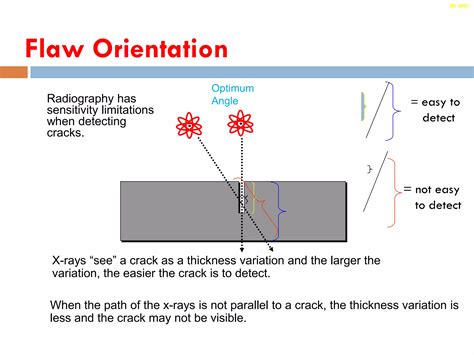

Projection geometry and consistency

Maintaining consistent projection geometry across studies enables meaningful comparisons over time. When projection angles vary, the orientation cues may appear misleading. A standardized protocol for positioning and projection selection supports diagnostic confidence.

Special projections and pitfalls

Some studies use oblique or angled projections to visualize structures obscured in standard views. These require careful documentation of the orientation and the reasoning for deviation. Awareness of common misorientation pitfalls helps reduce errors in Image Orientation Radiography.